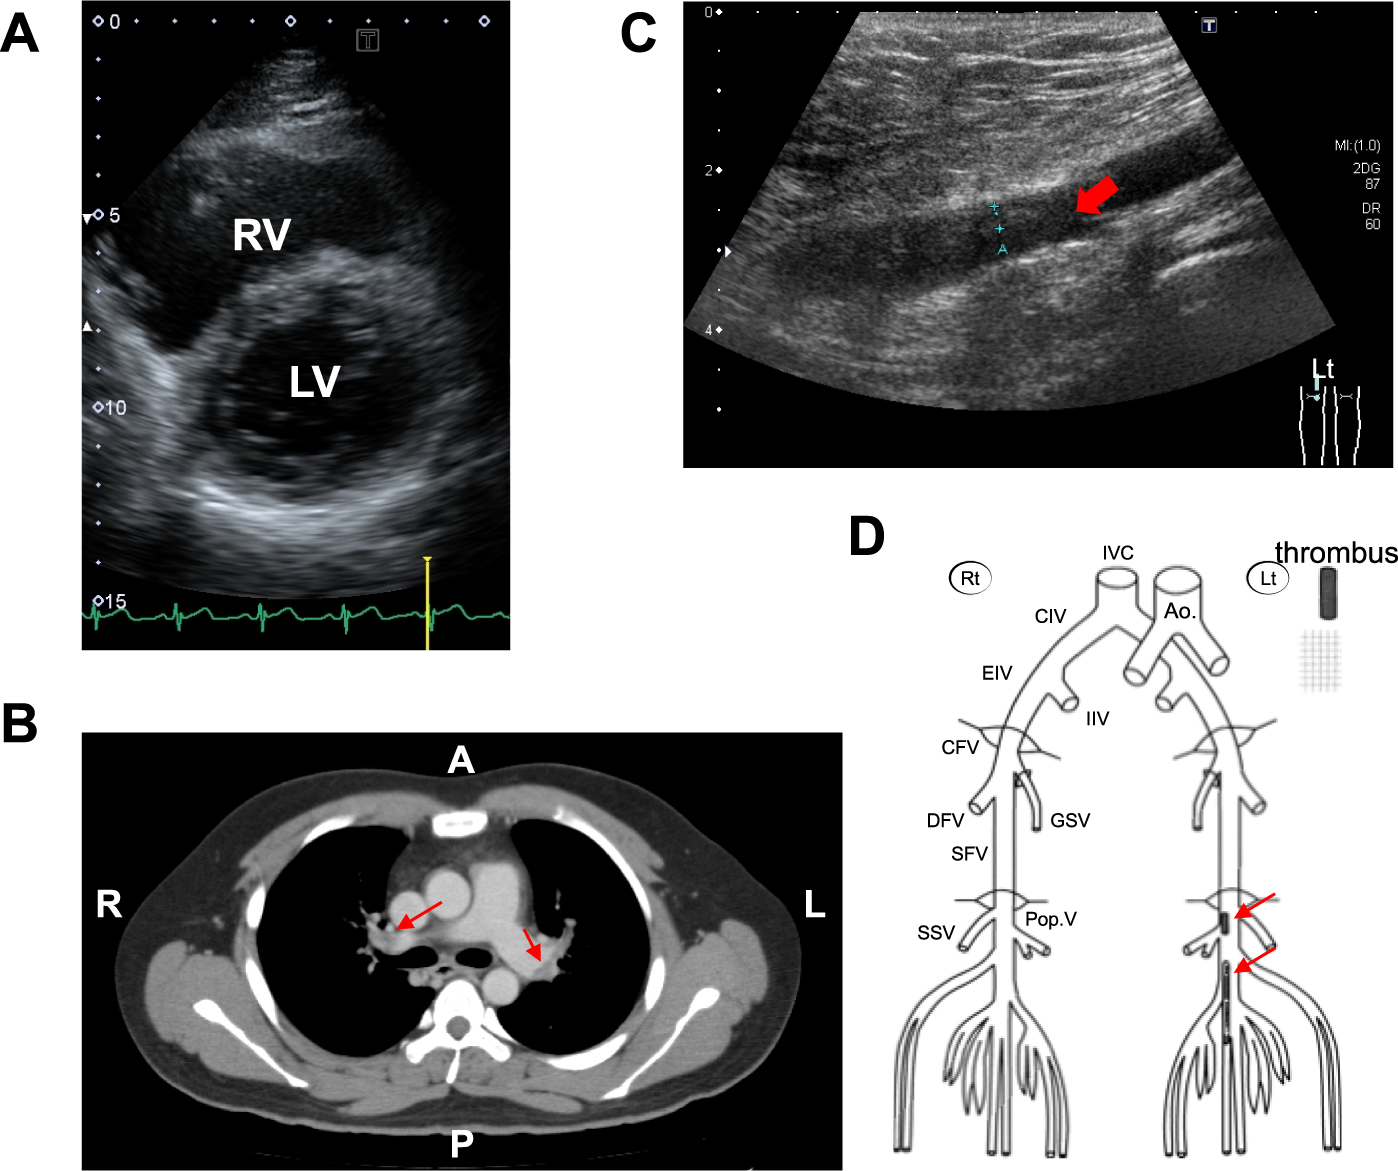

Fig. 1: Clinical assessment of the VTE patient.

A Right ventricular dysfunction found on echocardiography of the proband expressing the prothrombin p.R541W variant. RV, right ventricle; LV, left ventricle. B A thoracic CT scan showing multiple pulmonary embolisms (indicated by arrows) from the lobe branch level of the pulmonary artery to the peripheral part of the main pulmonary artery on both sides. C Venous ultrasonography of the left leg showing echogenic noncompressable thrombi on the center side of the left popliteal vein. D Schematic distribution of deep vein thrombi on the center side of the left popliteal vein and in the portion from the left popliteal vein to the center side of the peroneal vein, as indicated by arrows.